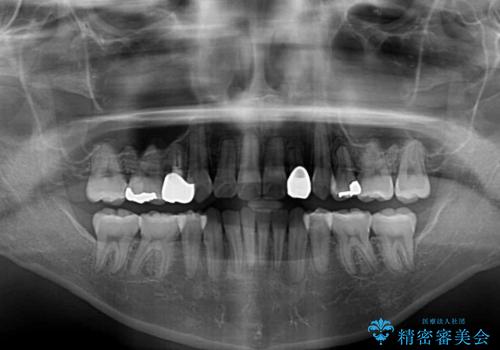

- 結婚式に向けて、八重歯と虫歯で変色した歯を改善したいとのことで来院された患者様です。

上下ともにデコボコが強いため、上下顎左右小臼歯各1歯を抜歯して歯列を整えることとしました。

大きな虫歯が認められた歯は、矯正治療後にオールセラミッククラウンにて補綴治療を行うこととしました。